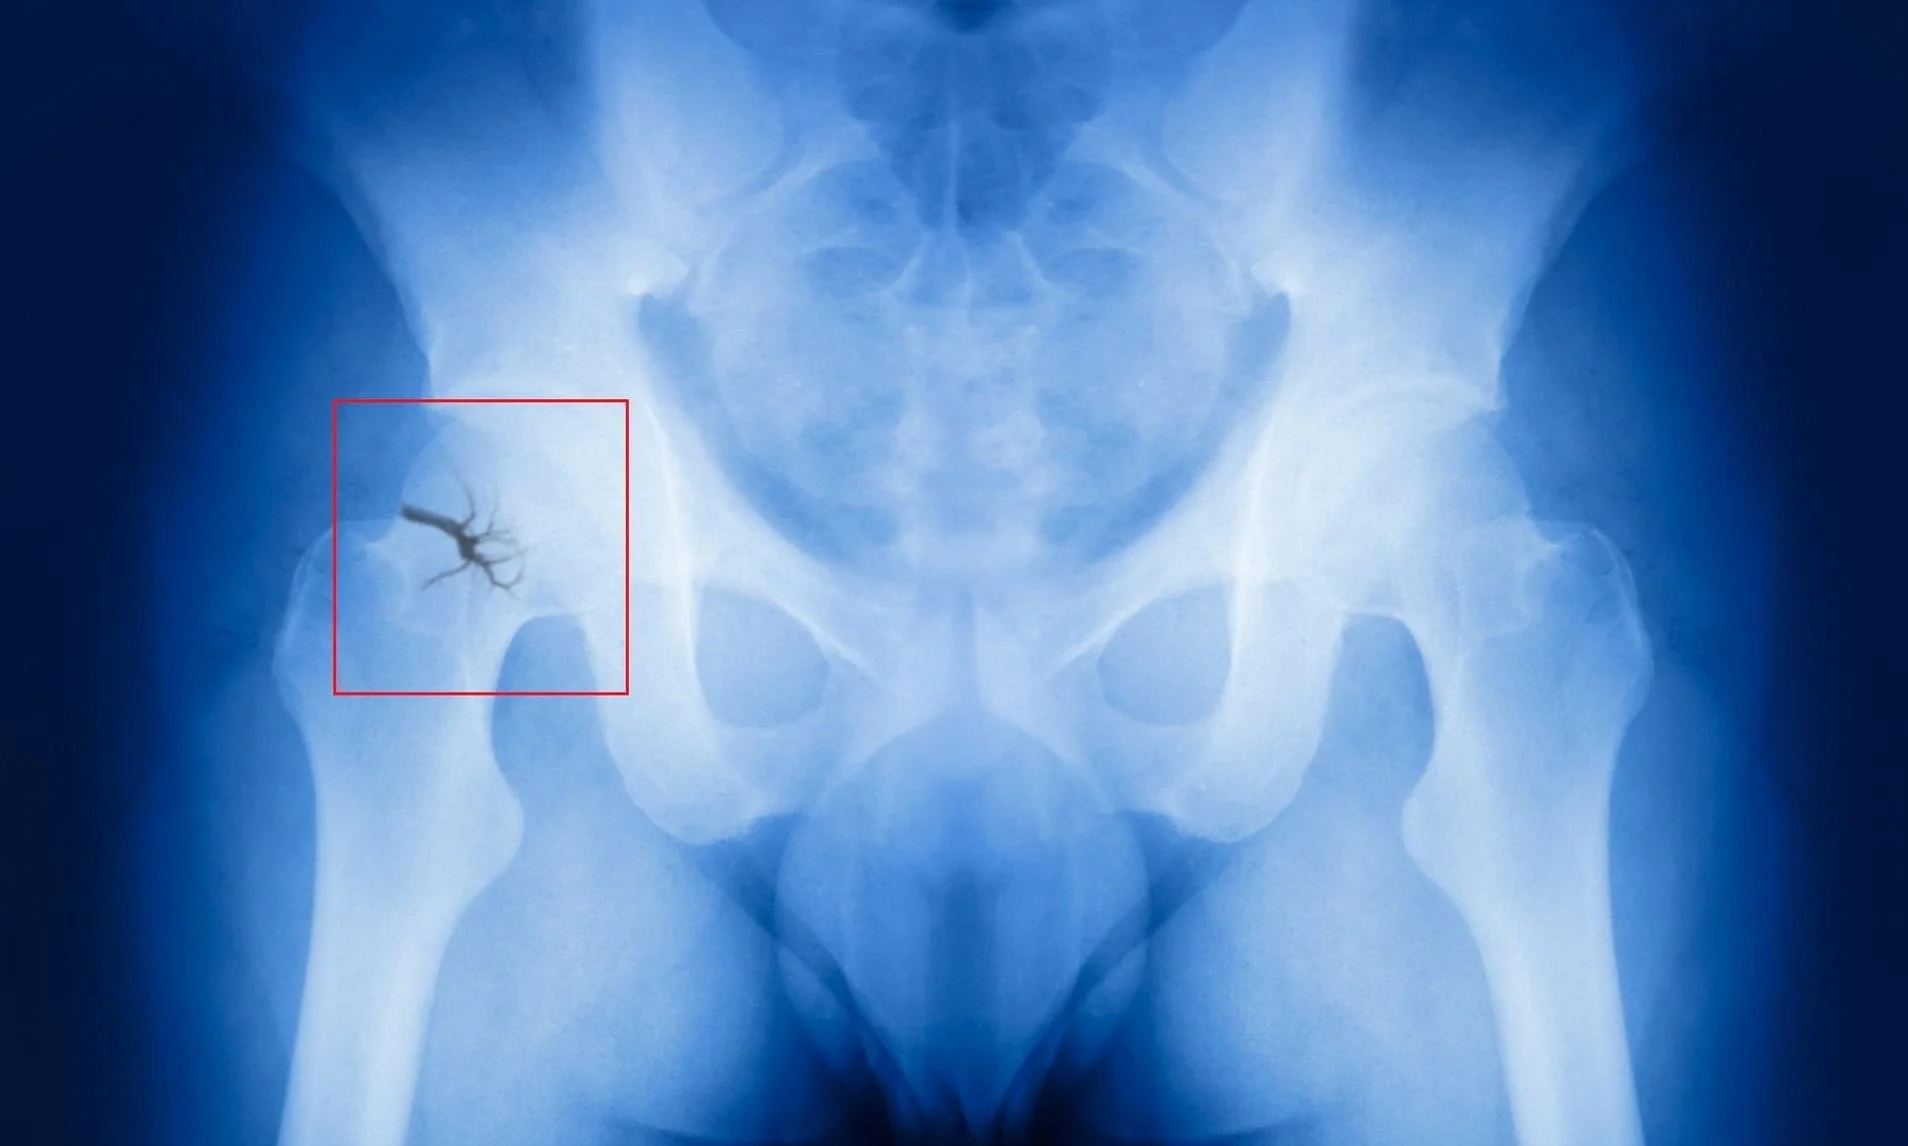

Falls & Fractures are a serious problem for the elderly population and account for a number of hospital admissions every year. Fractures of hips, wrist, pelvis and vertebrae can completely turn your life upside down as you struggle to cope with everyday activities that the rest of the world take for granted. This can have a knock on affect to your confidence and ability to go out and about. So you do a little less, you get a little bit weaker and frailer until you can no longer do the things you used to do without thinking. It doesn't have to be like that Back to Basics Physio can visit you at home to give you a personalised exercise program to work on your strength, mobility, confidence, balance. This will be progressive and push you to get back to what you loved doing before the fracture. If going out to the Supermarket, Bank, Post Office is daunting then I can work on this with you and practice at a pace that's manageable for you. Just give Back to Basics Physio a call to find out more!!